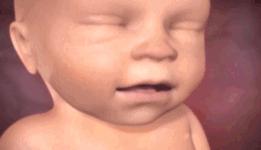

玩这么久了,好累,好困哦。

我要打个长长的哈欠。

不行,撑不住了,我要睡觉,你不许偷看哦。

哇,妈妈在吃什么呢?味道这么香,让我忍不住做梦的时候也在使劲咂嘴巴。

嗝,吃得太饱了,打个嗝先。